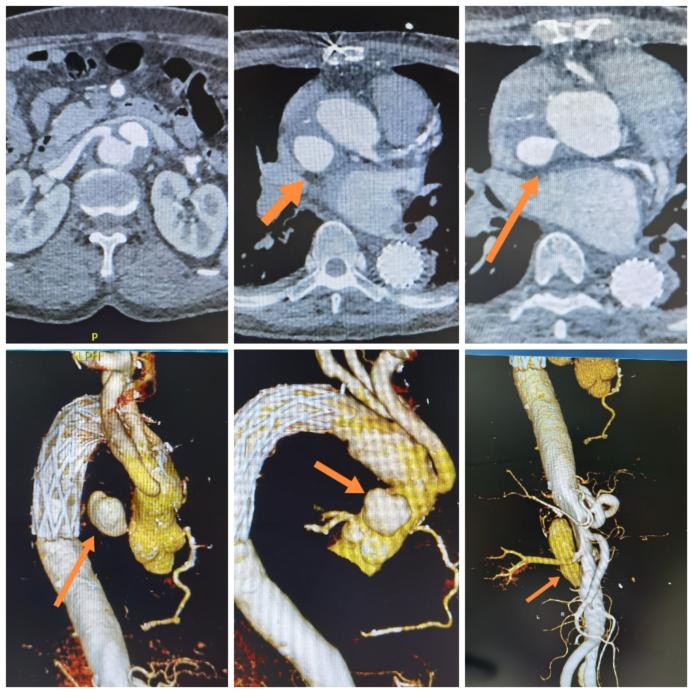

患者为51岁女性,2年前行主动脉弓置换加支架象鼻手术。此次因胸闷不适,行主动脉CTA(动脉血管成像)检查,提示升主动脉夹层动脉瘤,腹主动脉夹层。病变的复杂之处在于,升主动脉夹层动脉瘤破口位于升主动脉根部,破口直径约3mm,动脉瘤直径约3cm;自腹腔干动脉上方至左髂总动脉,腹主动脉全层撕裂,右肾动脉水平可见破口。

图1.术前CTA影像(箭头所指为升主动脉破口)